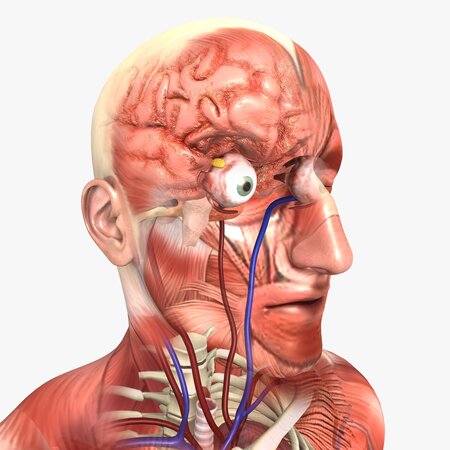

An aesthetic, accurate and easy to understand depiction of the very complex Human Urinary & Cardiovascular System

A transparent human model is included to give a sense of the organ's location, without cluttering the important details inside.

Arteries and Veins correctly marked in Red and Blue respectively.